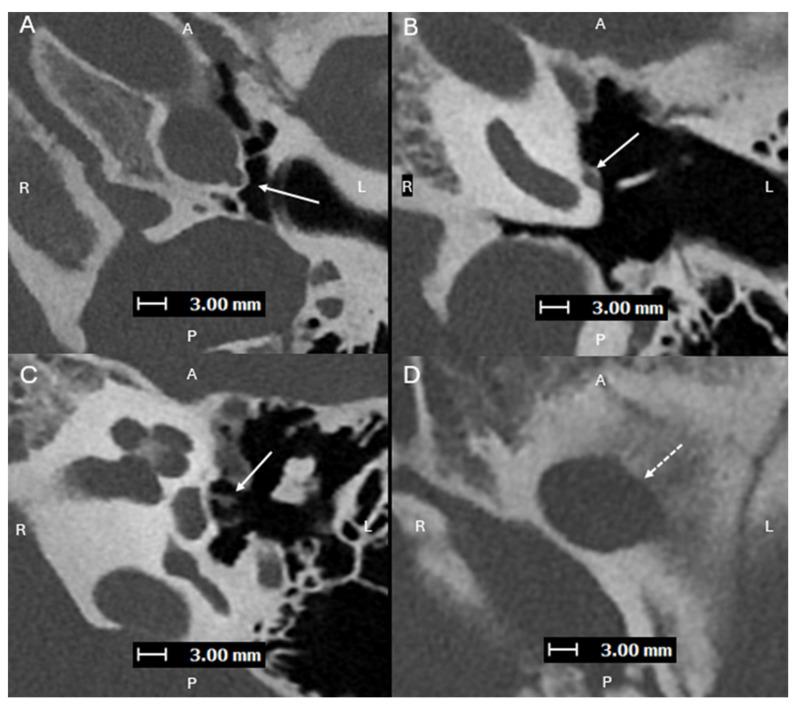

Aberrant internal carotid arteries (ICA) are congenital vascular anomalies that occur from involution of the cervical portion of the ICA, which leads to enlargement of the normally small collateral inferior tympanic and caroticotympanic arteries. The inferior tympanic artery is a branch of the external carotid artery, usually the ascending pharyngeal artery, which extends through the inferior tympanic canaliculus (ITC), a small foramen located along the cochlea promontory. Aberrant ICAs can also be associated with a persistent stapedial artery (PSA), which is an abnormal vessel that arises from the petrous ICA and passes through the obturator foramen of the stapes. An aberrant ICA is a very important anomaly to recognize on imaging. Accurately describing its presence is important to help prevent iatrogenic injury during intervention. It is also important to distinguish an aberrant ICA from a lateralized ICA. The improvement of spatial resolution with photon counting detector (PCD)-CT has been proven to provide higher performance in detection of sub-centimeter vascular lesions compared to conventional energy-integrated detector (EID)-CT. PCD-CT also provides superior visualization of small skull-based foramina such as the inferior tympanic canaliculus, which can aid in more accurately characterizing an aberrant ICA (variant course without ITC involvement).

异常颈内动脉(ICA)是一种先天性血管异常,由颈内动脉颈部的退化引起,导致通常较小的鼓室下和颈动脉鼓室侧支动脉扩张。鼓室下动脉是颈外动脉的分支,通常为咽升动脉,它穿过鼓室下小管(ITC),这是一个位于蜗窗岬附近的小孔。异常ICA也可能与镫骨动脉持续存在(PSA)有关,PSA是一条异常血管,起自岩骨段ICA,穿过镫骨闭孔。异常ICA是影像学上需要识别的非常重要的异常情况。准确描述其存在对于防止介入过程中的医源性损伤很重要。将异常ICA与侧位ICA区分开来也很重要。与传统的能量积分探测器(EID)-CT相比,光子计数探测器(PCD)-CT提高了空间分辨率,已被证明在检测亚厘米级血管病变方面具有更高的性能。PCD-CT还能更好地显示基于颅骨的小孔,如鼓室下小管,这有助于更准确地描述异常ICA(不涉及ITC的变异走行)。